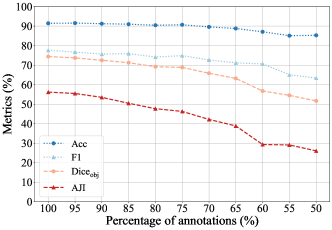

III-F Impact of the Completeness in Point Annotation

As an important component of our method, Voronoi diagram is based on two assumption: 1) the point annotation is at the center of the nuclei; 2) all the nuclei are labeled. The impact of the first assumption has been studied in Sec. III-E. This section investigates the robustness of the proposed model to the completeness of the point annotation. As shown in Fig. 7, to verify what level of completeness is required to train this model without a significant loss of performance, we gradually reduce the percentage of point annotations for training, and then test and calculate the segmentation metrics. When only 1% of the point annotations were missing, the segmentation metrics are only slightly reduced, as decreases from 74.41% to 74.18% and AJI decreases from 56.20% to 56.15%. As the percentage of annotations decreases, segmentation metrics reduce. However, our method can still maintain good performance when 15% of the annotations are missing. The missing of too many annotations will greatly reduce the accuracy of the generated coarse labels, and then lead to the reduction of segmentation performance.